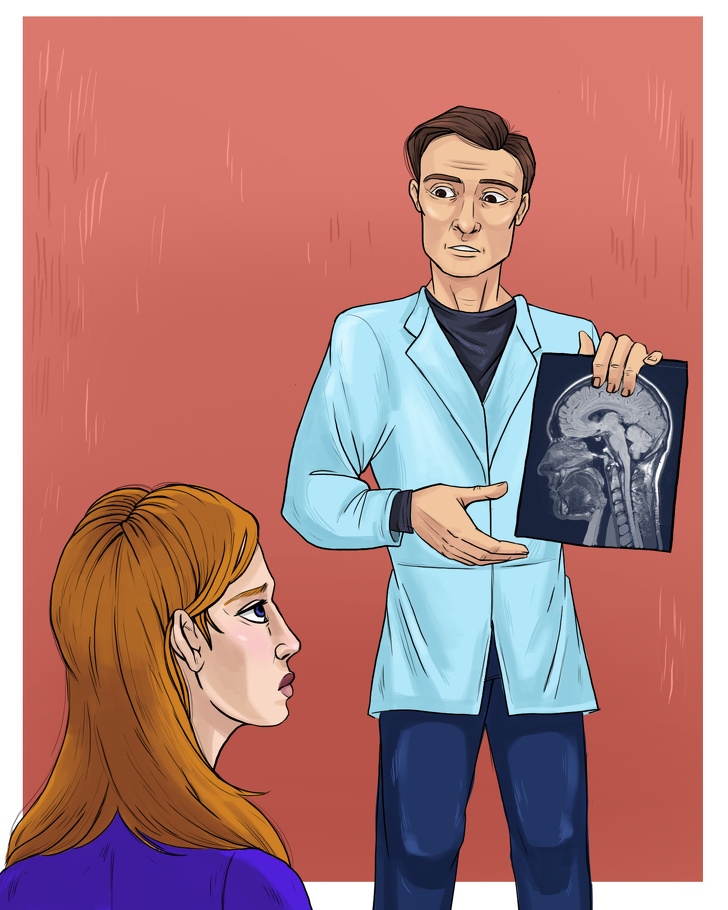

Αξιολόγηση κατάστασης και πρόληψη

Μπορείτε να μειώσετε τον κίνδυνο να πάθετε διάσειση φορώντας το σωστό κράνος κατά τη διάρκεια αθλητικών δραστηριοτήτων. Αλλά σε περίπτωση που έχετε υποστεί κάποιο ατύχημα, είναι σημαντικό να πάτε σε γιατρό και να κάνετε όλες τις απαραίτητες εξετάσεις για να βεβαιωθείτε ότι δεν έχετε διάσειση.

1. Επισκεφτείτε γιατρό για τη φροντίδα της διάσεισης.

4. Μόνο ένας επαγγελματίας υγείας μπορεί να αποφασίσει πόσο σοβαρή είναι η διάσειση και τους τρόπους αντιμετώπισης.